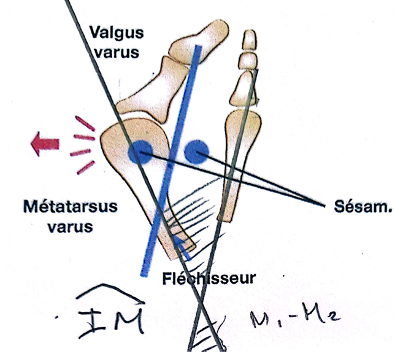

Figure 2 La déformation entraîné plusieurs anomalies

Lorsque les traitements conservateurs ne permettent plus de soulager les symptômes, une prise en charge chirurgicale peut être envisagée. Plusieurs techniques existent pour corriger l’hallux valgus. Parmi elles, l’ostéotomie bifocale percutanée représente une option intéressante dans les déformations importantes. Car cette technique corrige les 2 déformations essentielles :

a) le métatarsus varus qui se traduit par un angle M1 -M2 ou angle IM supérieur à 10° ( valeur normale < à 8°)

b) l’angle M1-P1 qui est supérieur à 20° (valeur normale de 8à 12° maximum 15°)

La première anomalie

Elle correspond à la déviation latérale du gros orteil, appelée valgus. Le gros orteil s’oriente progressivement vers les autres orteils, au niveau de l’articulation métatarso-phalangienne. Cette déviation modifie l’axe normal du premier orteil et perturbe son rôle essentiel dans la propulsion lors de la marche.

La deuxième anomalie

Elle concerne le déplacement du premier métatarsien vers l’intérieur du pied, phénomène appelé métatarsus primus varus. L’écartement progressif entre le premier et le deuxième métatarsien entraîne une perte d’alignement du premier rayon et contribue à l’aggravation de la déformation.

La troisième anomalie

Il s’agit de la «bosse» ou «l’exostose». Son siège est dorso-médial, en regard de la tête du premier métatarsien.

Elle correspond à l’hypertrophie médiale de la tête du premier métatarsien. C’est une proéminence osseuse qui est visible sur le bord interne du pied et forme ce que l’on appelle communément un « oignon ». Il ne s’agit pas d’une excroissance osseuse indépendante, mais plutôt de la conséquence de la déformation et de la saillie de la tête métatarsienne devenue plus apparente.

À ces anomalies osseuses s’ajoutent également des modifications des tissus mous autour de l’articulation. Les ligaments, la capsule articulaire et les tendons se déséquilibrent progressivement. Certains se rétractent tandis que d’autres se distendent, ce qui entretient et accentue la déviation du gros orteil.

La déformation est également favorisée par un déséquilibre des structures musculaires et tendineuses qui stabilisent l’articulation métatarso-phalangienne. Certains tendons, notamment ceux situés sur le versant latéral de l’articulation, peuvent exercer une traction qui accentue progressivement la déviation du gros orteil. Ce déséquilibre entretient et aggrave la déformation au fil du temps.

Enfin, la déformation entraîne souvent une subluxation des sésamoïdes, deux petits os situés sous la tête du premier métatarsien. Leur déplacement modifie l’équilibre de l’articulation et perturbe le fonctionnement normal du système d’appui.